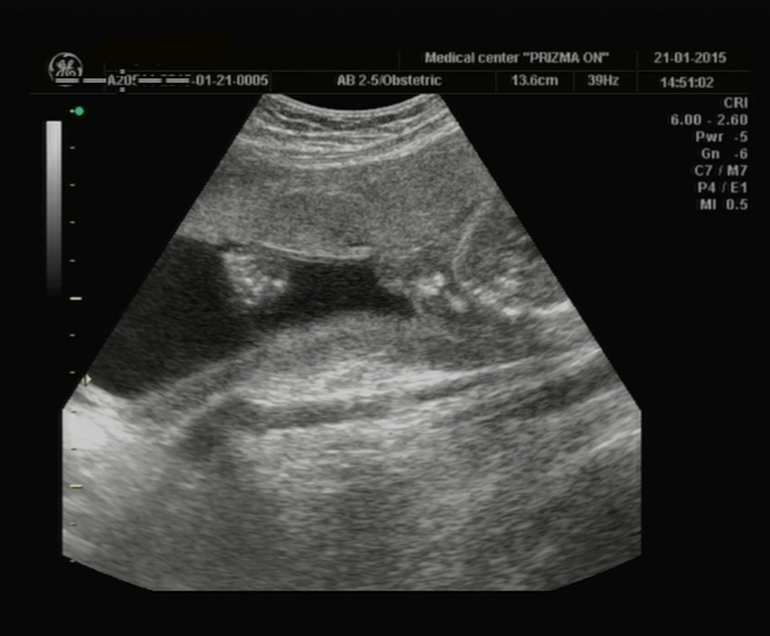

Сдали мы кровь, на второй скрининг, всё у нас хорошо. Сделали УЗИ, ровно в 20 недель, всё у нас в норме. Теперь малыш отстаёт на 3 дня, от для М и поставили нам 19 недель 5 дней, но в заключении указали 20 ровно недель... Сказали что мальчик, но нашли только мошонку. Теперь жду следующего УЗИ 24й неделе, схожу в другое место, может там нам малыш всё таки решит показать кто он, а то всё время ножки зажимает...

Наши ножки